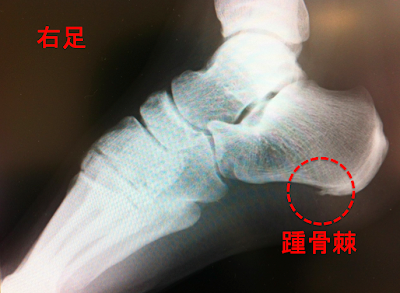

足底腱膜炎で一番こわいのは、足底腱膜の踵の付着部に骨棘(こつきょく)が出きてしまうものです。

骨棘とは踵にとげができてしまう状態です。

レントゲンを撮ると上の写真の様な状態です。

このとげが当たる事で痛みを感じてしまいます。

足底腱膜のテンションがかかり過ぎると、腱に引っ張られ続けたかかとの付着部が強度を高めるためにカルシウムが沈着していきます。

このカルシウムが集まって骨の様に硬い棘を形成していくため、骨棘と呼ばれます。

この骨棘は一度できてしまうとなくすためには

手術をして削る方法しかありません。